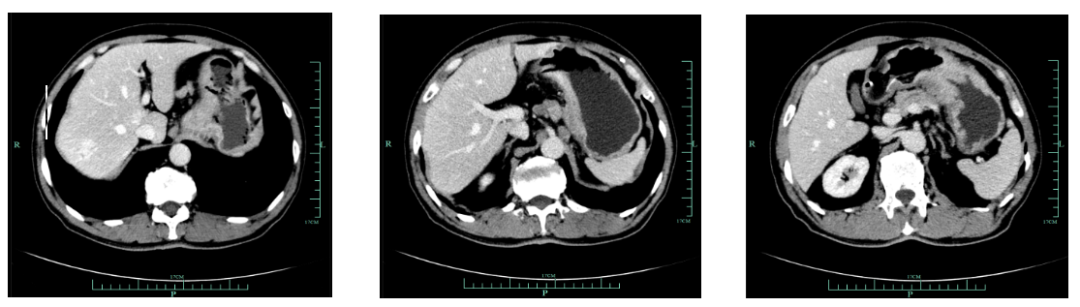

2018-12-20至2019-2-21,SOX Q3W 4周期,具体为奥沙利铂230mg D1,替吉奥3# BID D1-14 ,疗效评估为缩小的SD。

一线化疗疗效评估(2019.6 vs 2019.4):胃癌术后改变。影像评估CR。

由于奥沙利铂8个周期化疗结束,2019-6-26至2019-11-29行S-1+赫赛汀 q3w 8周期联合维持治疗:替吉奥3# BID D1-14、赫赛汀 300mg D1。

影像学评估:胃癌术后改变。持续CR。